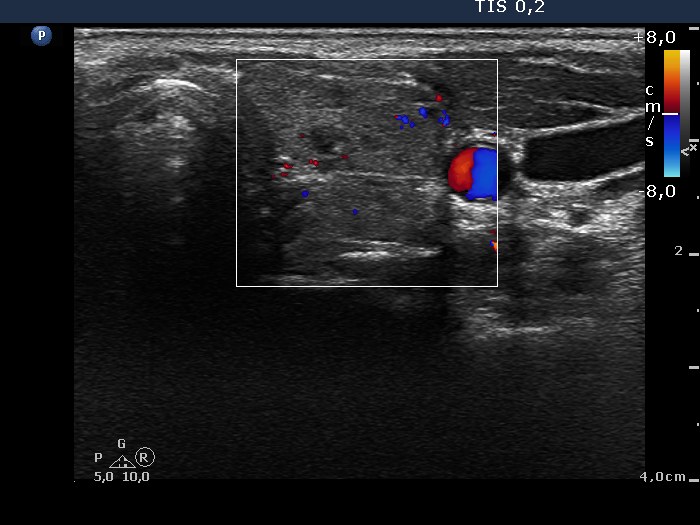

Chronic lymphocytic thyroiditis - Case 24. (ultrasonographic picture 6)

Left lobe, horizontal scan, color Doppler mode. The vascularization is decreased.